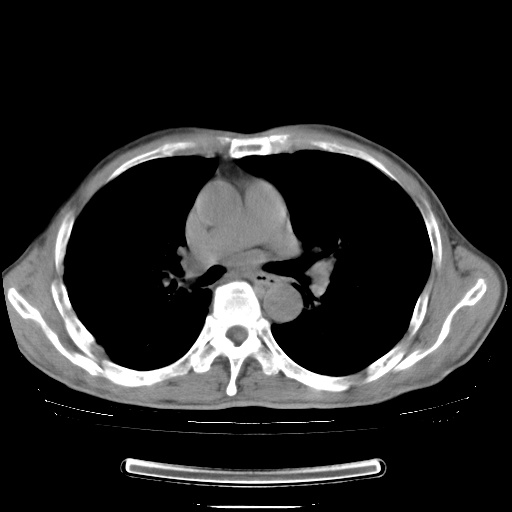

男性患者,63岁。右侧胸背部疼痛2月,加重一周。

考虑:右肺中央型肺癌并右肺下叶不张;两肺尖继发性肺结核。

还有纵隔多处肿大淋巴结及肋骨的改变、两肺多发结节灶。

右肺下叶支气管狭窄闭塞,右下肺不张,气管前间隙淋巴结肿大,两上肺散在分部粟粒灶,沿肺血管支气管束分部,血管支气管束走形较为光滑。考虑右肺中心型肺癌合并肺不张,纵隔淋巴结转移,两上肺癌性淋巴管炎